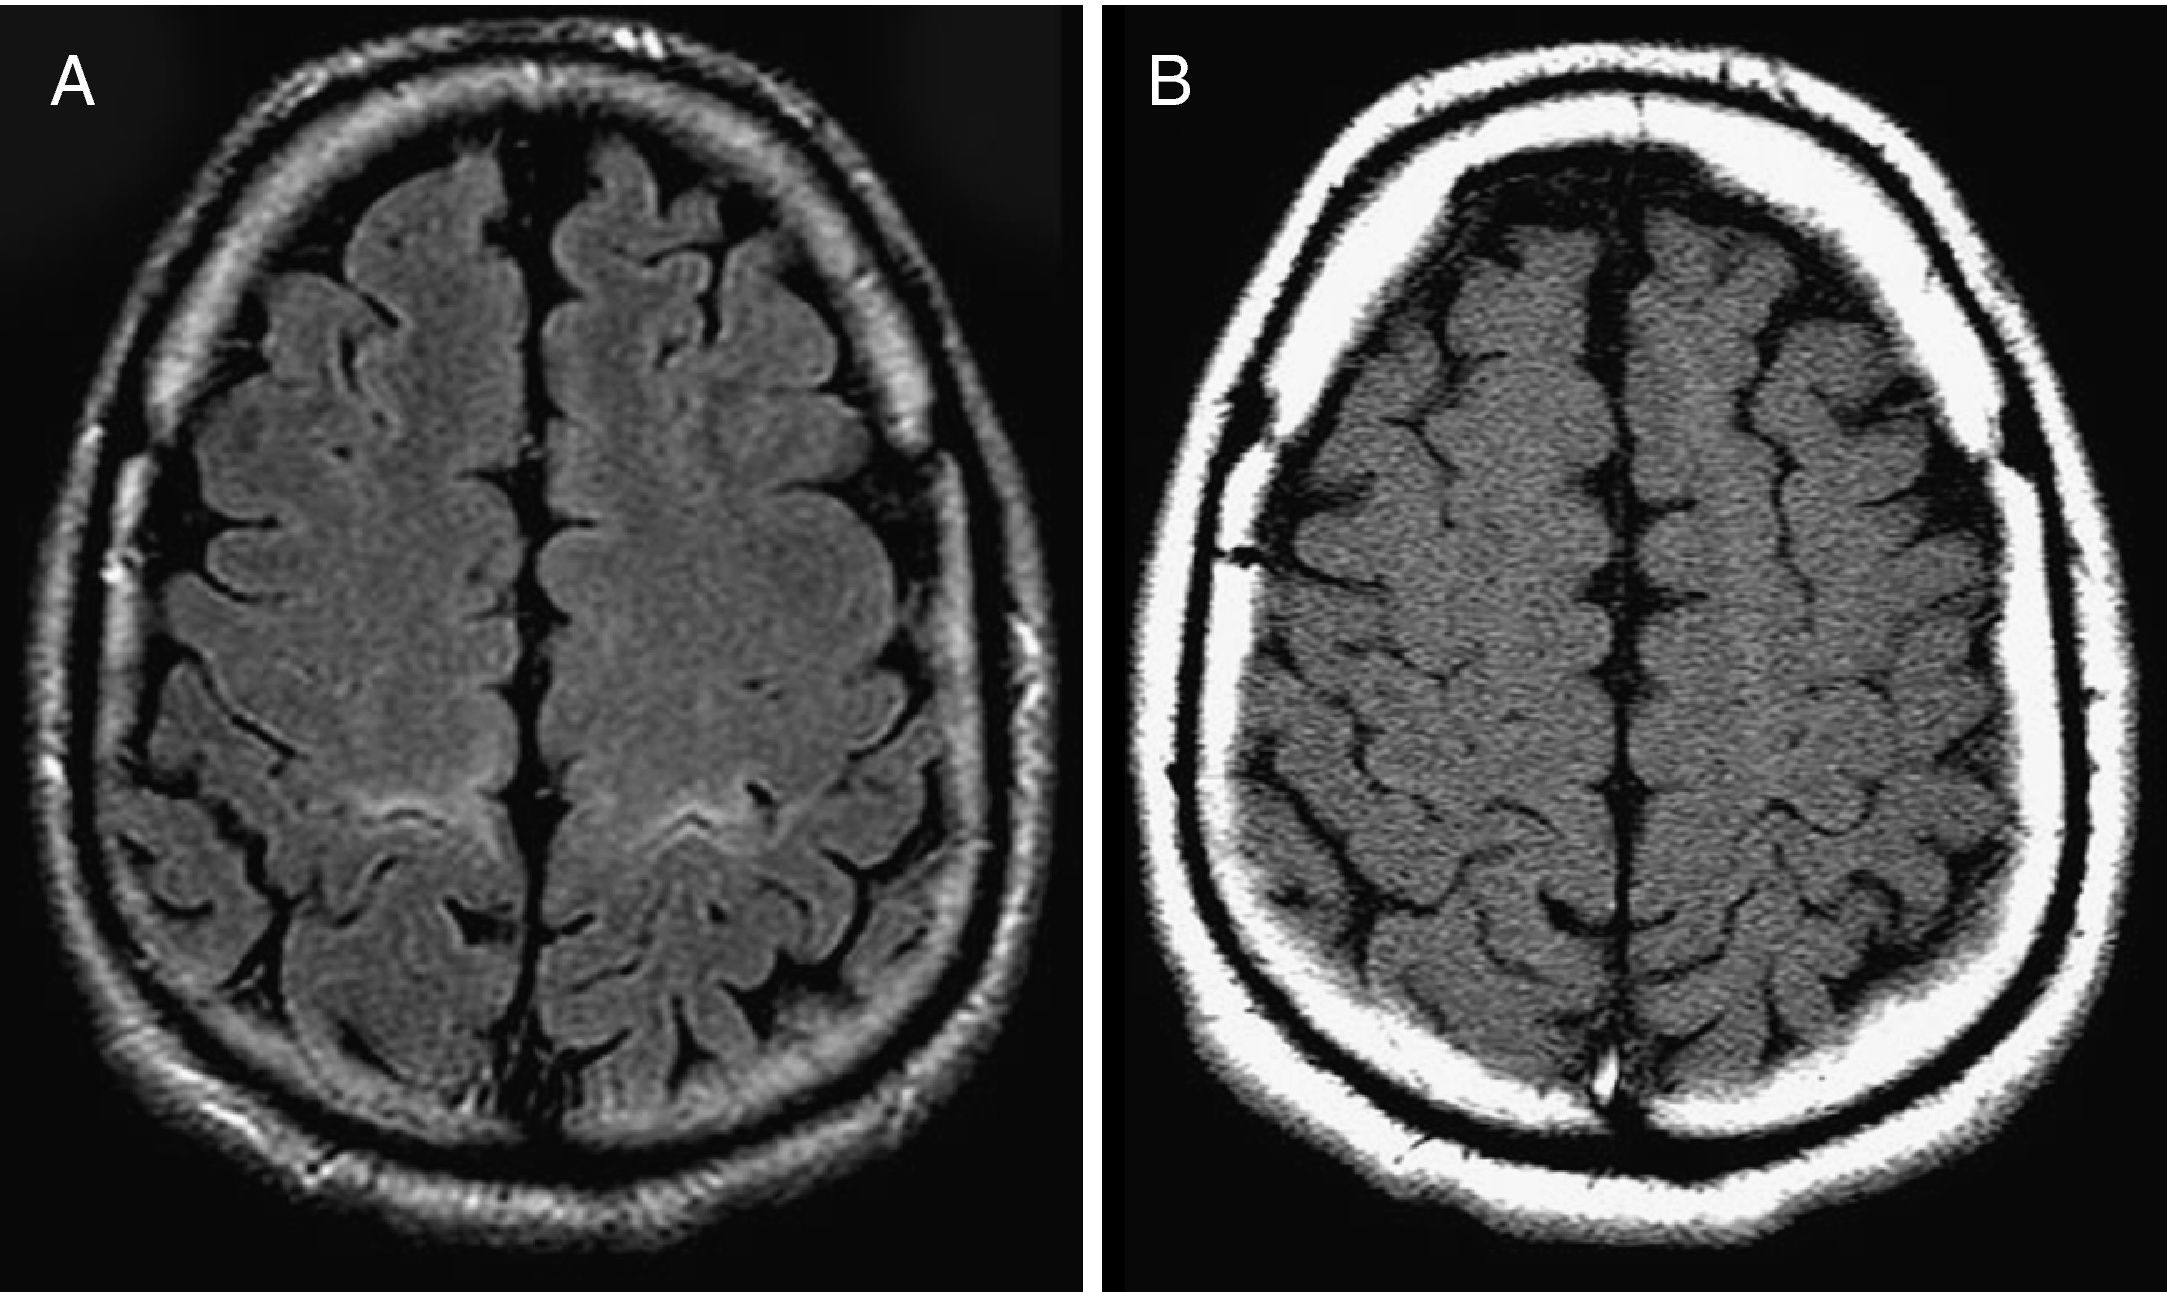

Carga mundial, regional y nacional de la epilepsia, 1990-2021:  análisis sistemático para el Estudio de la Carga Mundial de Enfermedades 2021

Aunque las tendencias mundiales en cuanto a muertes por epilepsia idiopática y tasas de AVAD han mejorado en las décadas anteriores, en 2021 había casi 52 millones de personas con epilepsia activa (24 millones por epilepsia idiopática y 28 millones por epilepsia secundaria), y la mayor parte de la carga (>80%) reside en países de ingresos bajos a medios. Se requieren mejores tratamientos y prevención de la epilepsia, junto con más investigaciones sobre los factores de riesgo de la epilepsia idiopática, estudios de vigilancia de la epilepsia a largo plazo de buena calidad y exploración del posible efecto del estigma y las diferencias culturales en la búsqueda de atención médica para la epilepsia. The Lancet Public Health, 24 de febrero de 2025